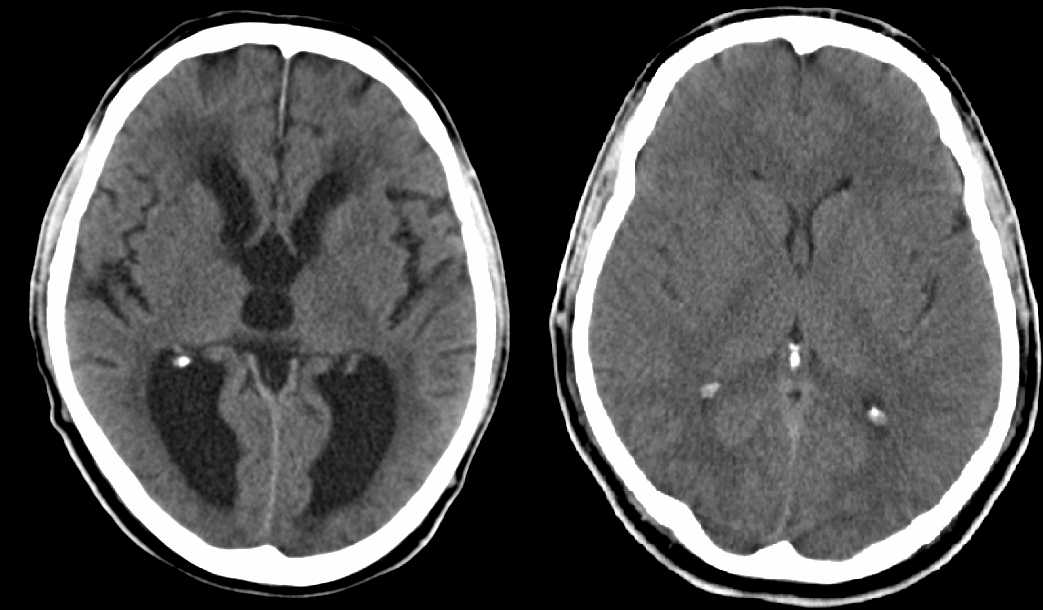

Sie sind hier: Startseite Nachrichten Gesundheit Arbeitsfähig bei 90 Prozent Hirnschwund – ein Rätsel für Wissenschaftler links CT eines Hydrocephalus internus; rechts zum Vergleich ein normales Gehirn.

links CT eines Hydrocephalus internus; rechts zum Vergleich ein normales Gehirn.